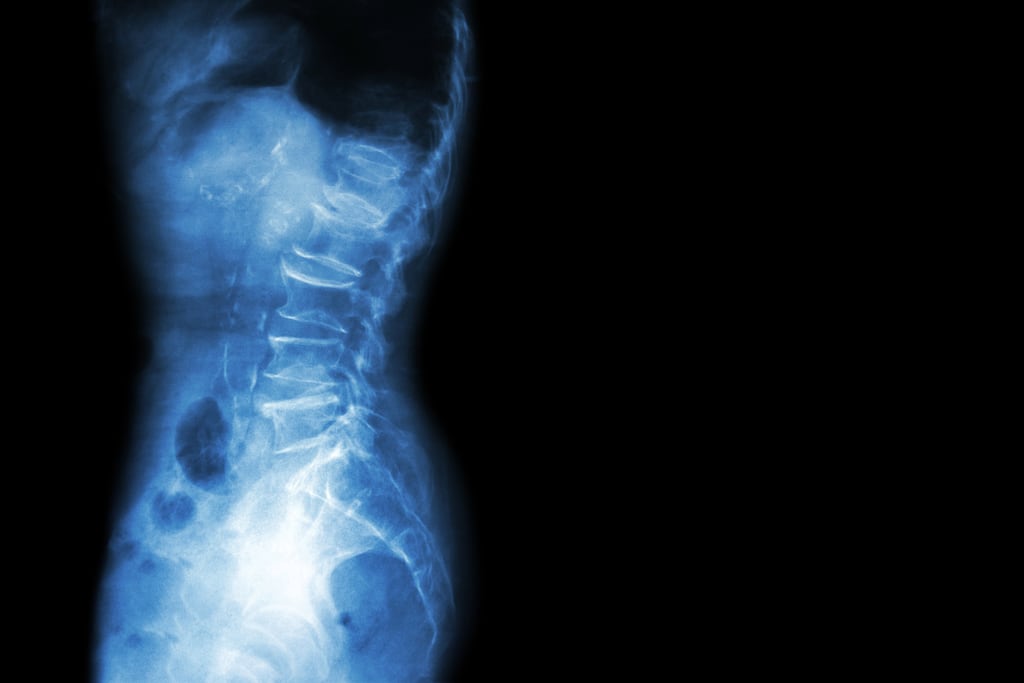

- Axial spondyloarthritis (axSpA) is an inflammatory form of arthritis where the main symptom is back pain and changes can be seen to the sacroiliac joints on X-rays.

- It is a painful, chronic inflammatory disease, which primarily affects the spine and sacroiliac joints. However, feet, knees and ankles can also experience pain and stiffness, along with other symptoms such as sclerosis, inflammatory bowel problems and uveitis.

- The main symptom is inflammatory back pain, but some people also experience pain, stiffness and limited mobility outside of the spine, such as in their neck, shoulders, hips, chest, knees and even heels. Morning stiffness and pain can also occur, typically wearing off during the day, particularly with activity and movement.